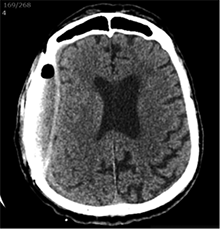

Po 2 savaičių pacientas rastas parkritęs kieme. Buvo matyti kraujuojanti žaizda. Pacientas pakartotinai hospitalizuotas į Neurochirurgijos skyrių. Atlikus GKT, nustatyta 25 mm storio hipodencinė juosta virš dešiniojo smegenų pusrutulio ir 8 mm vidurinių smegenų struktūrų dislokacija (VSD) į kairę (3 pav.). Įtariant lėtinę SDH dešinėje pusėje, pacientas reoperuotas, atliekant rekraniotomiją. Operacijos metu ant kietojo smegenų dangalo (KSD) rasta fibrino, jis pašalintas. Pravėrus KSD, rastas drumstas turinys, nesant aiškių pūlių, ir stora kapsulė. Gausiai praplauta šiltu fiziologiniu tirpalu subduraliai. Kaulinis lopas grąžintas (4 pav.). Po operacijos pacientas pradėjo skųstis stipriu galvos skausmu, tapo vangus. GKT pakartota. Įtarta empiema, nustatyti oro tarpai subduraliai, galvos smegenų VSD – 6 mm. Praėjus 12 dienų po antros operacijos, pacientas operuotas pakartotinai. Operacijos metu atlikta rekraniotomija. Epiduriniame ir subduriniame tarpuose rasta pūlių ir fibrino. Pūliai ir fibrinas pašalinti, paimtas bakteriologinis pasėlis. Žaizda gausiai praplauta šiltu fiziologiniu tirpalu. Kaulinis lopas negrąžintas, minkštieji audiniai susiūti (5 pav.). Po operacijos paciento būklė stabilizavosi. Bakteriologiniame pasėlyje negausiai užaugo E. coli, jautri ampicilinui. Nesant teigiamo efekto gydant ampicilinu, dar 2 savaites pacientui skirta gentamicino. Praėjus 3 savaitėms po trečios operacijos, pacientas perkeltas į slaugos ligoninę palaikomojo gydymo.

4 pav. Po antrosios operacijos (didžioji hematomos dalis pašalinta; VSD sumažėjo nuo 8 iki 5 mm)